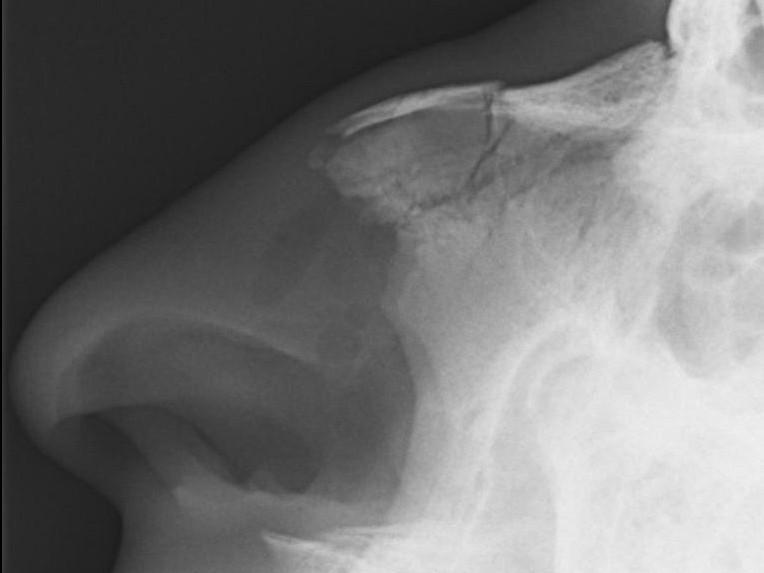

Fracture des os propres du nez

Radio

des OPN et consultation différée

3 à 5 jours